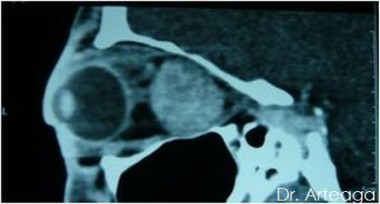

Galería de Imágenes